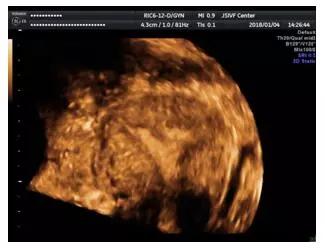

三维超声成像的宫腔粘连

文献中EI-Mazny等报道经阴道三维超声诊断宫腔粘连的特异性达100%,但敏感性仅41.7%,但Fedele等认为经阴道超声特异性为100%,敏感性为91%。Narayan等认为经阴道三维超声能监测出98.9%的有子宫内膜病变的患者。Knopman等对比评价经阴道三维超声,子宫输卵管碘油造影,宫腔镜的准确性发现,子宫输卵管碘油造影的敏感性为66.7%,经阴道三维超声的敏感度为100%,认为经阴道三维超声可对粘连严重程度的分型提供依据,其较输卵管碘油造影能提供更精确地子宫腔病变及粘连的范围。

总结:三维超声检查可用于宫腔粘连的诊断,但三维超声检查仍存在一定程度的漏诊率及误诊率,宫腔镜检查可进一步明确诊断。三维超声虽然不能确诊不同程度宫腔粘连,但可为宫腔镜手术提供有价值的参考信息。超声检查具有无创,相对简单易行等优点,临床推荐用于宫腔镜手术前的筛查。